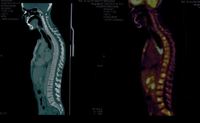

PET CT showed multiple hypermetabolic marrow lesions seen involving the axial skeleton. Multiple hypermetabolic left cervical bilateral left cervical and bilateral subpectoral and mediastinal nodes were also noted. On clinical suspicion of lymphoma bone marrow aspirate was reported elsewhere with maroow plasmacytosis of 15% and bone marrow  biopsy was done and sent.